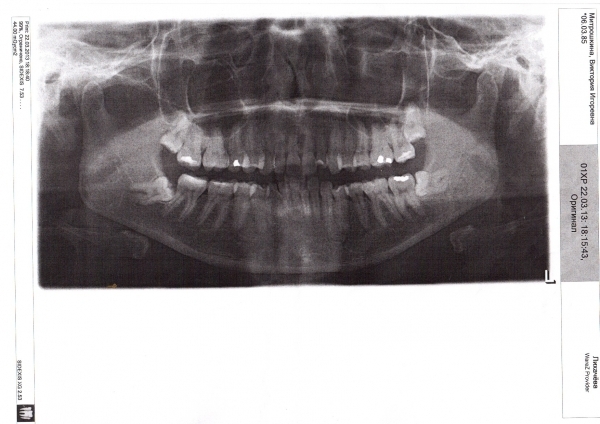

У меня некоторые зубы кривые, как сказали врачи, из-за зубов мудрости. Верхние удалили и хочу на верхнюю челюсть поставить брекеты, а на нижнюю, наверное, не стоит, т.к. там лежат почти в десне боком зубы мудрости слева и справа. Высылаю фото, верхние восьмерки удалены, остались нижние.

Возможны ли брекеты только на верхнюю челюсть или что-то другое? Т.к. зуб сильно торчит (см. фото № 3).

К сожалению, выравнивание только верхней челюсти не даст нужных результатов. Ведь смысл ортодонтического лечения кроется не только в ровном зубном ряду. Главное, что должно Вас беспокоить — неправильный прикус, что в более зрелом возрасте доставит Вам много проблем.

Ортодонтическое лечение показано на обеих челюстях, однозначно. Не стоит делать неправильных шагов, Вы потратите средства и не получите результатов.

Обратитесь к нам на очный приём к хирургу, имеющему большой опыт в удалении данных зубов. Да — это сложно, да — это дорого, но Вам все равно придётся это сделать рано или поздно. В противном случае Вы потеряете седьмые зубы.